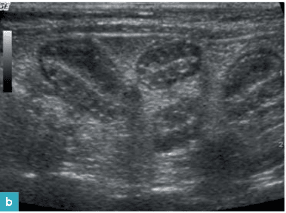

9. Ecografía de los riñones y uréteres

Técnica ecográfica

Ecografía de riñones y uréteres normales

Ecografía de las patologías renales y ureterales